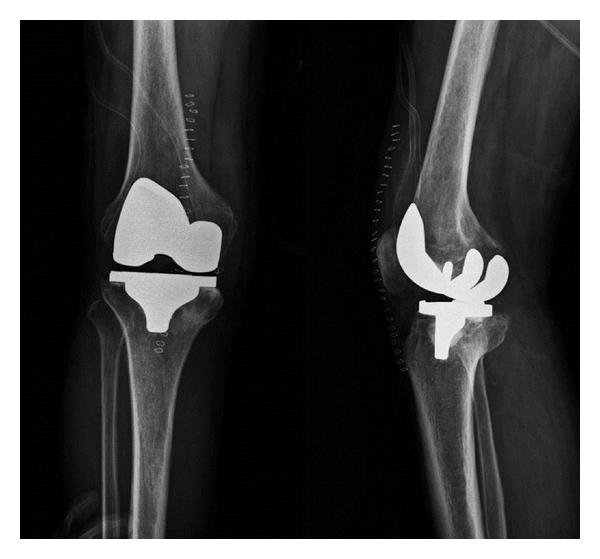

Isolated primary candidal infection of joint is extremely rare, with only a few reported cases. It occurs as a result of accidental implantations of fungus during traumatic procedures, such as surgery, and is usually reported in patients with predisposing factors such as immunosuppression, malignancy, and drug abuse. If left untreated, irreversible deformity and pain with severe osteoarticular destruction occur. Thus, early diagnosis and treatment are important. This paper presents a case of 72-year-old man with primary C. guilliermondii infection of knee joint without predisposing factors and previous traumatic procedures, who was misdiagnosed with advanced degenerative osteoarthritis. Our case is the second case of primary C. guilliermondii arthritis of knee to be reported in the English-language literature and the first to be successfully treated with total knee arthroplasty following IV amphotericin B and oral fluconazole. Primary candidal infection of joint is generally asymptomatic or involves only mild pain and swelling in the affected knee. Thus, although the majority of knee joint infections are of a pyogenic or tuberculous origin, if a patient complains of mild pain and swelling in the knee and has mild signs of infection, the possibility of fungal infection should be considered.

孤立性原发性关节念珠菌感染极为罕见,仅有少数病例报道。它是在诸如手术等创伤性操作过程中真菌意外植入所致,通常见于有免疫抑制、恶性肿瘤和药物滥用等易感因素的患者。若不治疗,会出现不可逆畸形以及伴有严重骨关节破坏的疼痛。因此,早期诊断和治疗很重要。本文介绍了一例72岁男性患者,其膝关节原发性季也蒙念珠菌感染,无易感因素且既往无创伤性操作史,曾被误诊为晚期退行性骨关节炎。我们的病例是英文文献中报道的第二例膝关节原发性季也蒙念珠菌关节炎病例,也是首例在静脉注射两性霉素B和口服氟康唑后成功接受全膝关节置换术治疗的病例。关节原发性念珠菌感染通常无症状,或仅累及患膝轻度疼痛和肿胀。因此,尽管大多数膝关节感染起源于化脓性或结核性,但如果患者诉说膝关节轻度疼痛和肿胀且有轻度感染体征,应考虑真菌感染的可能性。